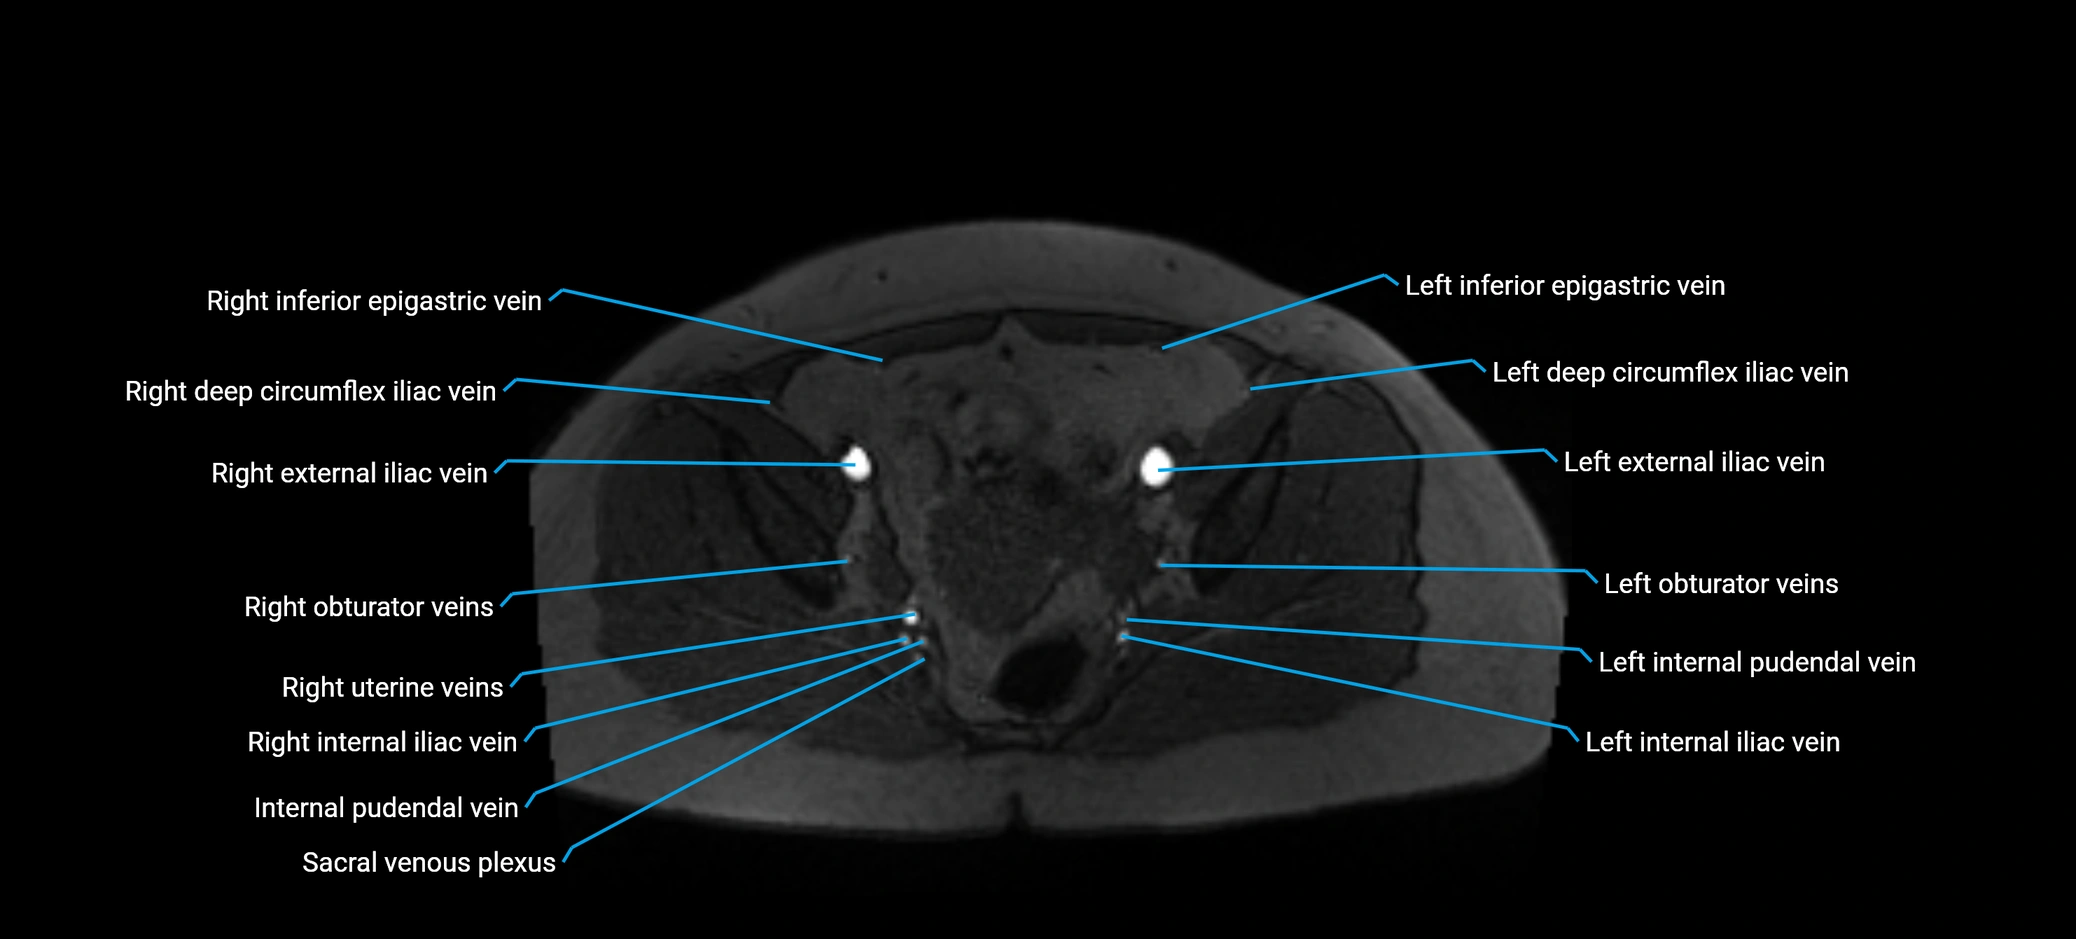

MRI image

image